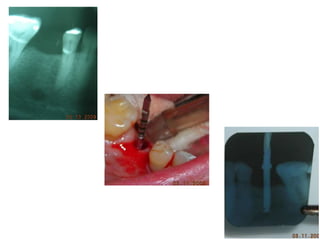

Dogmar Dasgupta,March,2009

Immediately after operation

On 11th.March,2009.